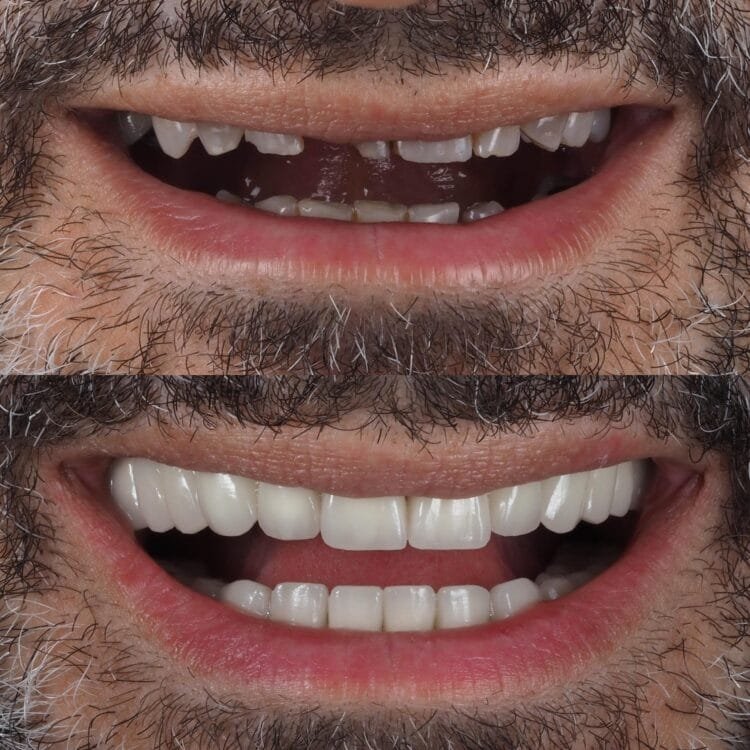

Antalya Privatklinik

Ich habe in einer Klinik für Gesundheitstourismus in Antalya gearbeitet und dabei umfangreiche Erfahrungen in der ästhetischen und prothetischen Behandlung gesammelt, wobei ich hauptsächlich mit internationalen Patienten gearbeitet habe.

Durch meine Arbeit im Gesundheitstourismus habe ich ein Verständnis entwickelt, das eine effektive Kommunikation und hohe Zufriedenheit mit Patienten aus verschiedenen Kulturen gewährleistet. Seien Sie ein Partner in diesem Vertrauen.

Ich plane speziell für die Bedürfnisse jedes einzelnen Patienten und arbeite akribisch bis ins kleinste Detail, um Ihnen ein natürliches und ästhetisches Lächeln zu ermöglichen.